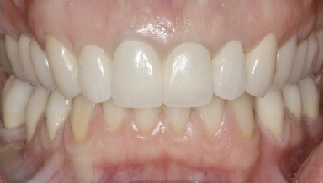

Проблема. Старые, неэстетичные металлокерамические коронки, стёртые зубы, глубокий прикус.

Решение. Проведено протезирование зубов керамическими коронками из диоксида циркония, а также была увеличена высота прикуса.